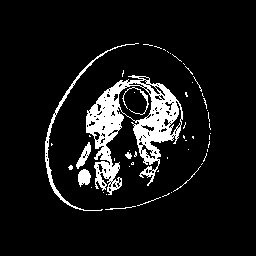

Finally, we define the set of corrected pseudo-labels as the intersection between the and masks. Examples are shown in Fig. 2.

(a) Image

(b)

(c)

(d)